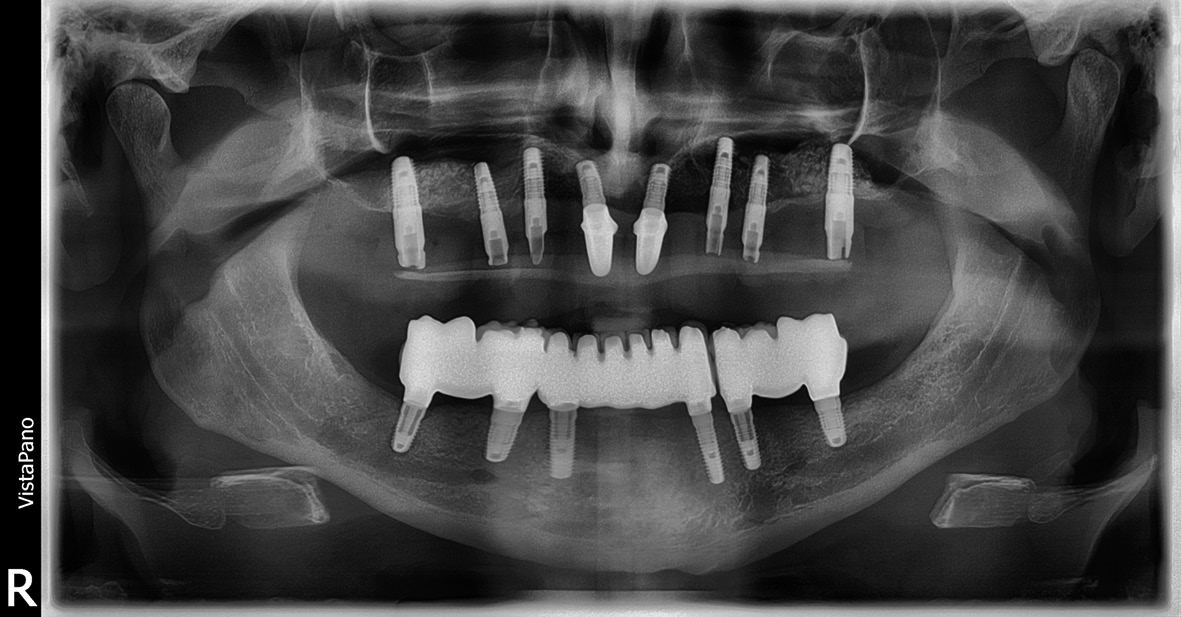

- Virtuelle Planung der möglichen Implantatpositionen und Evaluation, ob eine festsitzende Versorgung ohne Beckenkammaugmentation durchführbar ist. Die Analyse ergab, dass eine Versorgung im Oberkiefer mit acht Implantaten und im Unterkiefer mit sechs Implantaten für ein festsitzendes Zahnersatz-Konzept zwar implantologisch anspruchsvoll, aber durchführbar wäre. Daraufhin wurden die optimalen Implantatpositionen sowohl in Bezug auf den verfügbaren Knochen als auch das prothetische Ziel definiert und in der Planungssoftware (coDiagnostiX) festgelegt (Abb. 3-5).

Die Schablonen wurden in einem 3D-Druckverfahren hergestellt und mit Bohrhülsen für das Camlog Guide System versehen (Abb. 8-9). Hierbei handelt es sich um ein speziell abgestimmtes Bohrersystem zur sog. „full guided“ Implantation, d. h. nicht nur alle Bohrschritte von der Pilotbohrung bis zur fi nalen Aufbereitung und ggf. Gewindeschnitt, sondern auch die Implantatinsertion wird durch die Schablone durchgeführt. Intraoperativ wurde zunächst ein Mukoperiostlappen zur Darstellung des krestalen Knochens präpariert, was eine sichere und reproduzierbare Positionierung der Schablonen auf den Knochenauflagen ermöglichte. Danach erfolgte die full guided Insertion von Camlog Implantaten mit dem Camlog Guide Abb. 7: Planung der UK-Bohrschablone (Labor Cera-Technik, München). Abb. 8: OK-Bohrschablone mit eingearbeiteten Bohrhülsen (Labor Cera-Technik, München). Abb. 9: OK-Bohrschablone von basal mit den Knochenauflagen (Labor Cera- Technik, München). Abb. 10: Full guided Insertion der Implantate durch die Schablone. Bohrersatz in regio 16, 14, 13, 11, 21, 23, 24, 26 sowie 36, 34, 33, 43, 44, 46 (Abb. 10-12). Schon während der virtuellen Planung wurde dabei das Ausmaß ggf. zusätzlich notwendiger Augmentationen festgelegt und es erfolgte nach Abnahme der Schablonen an den geplanten Stellen autologe Augmentationen mit autologen Knochenblöcken (Abb. 13- 14).